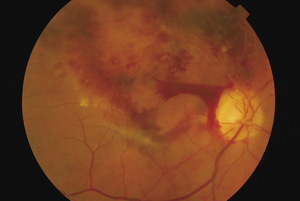

Rycina 4. Zamknięcie gałązki skroniowej dolnej tętnicy środkowej siatkówki z towarzyszącą ischemią siatkówki

Krwawienia, ogniska waty, obrzęk, zamknięcie światła naczynia (ryc. 4) |